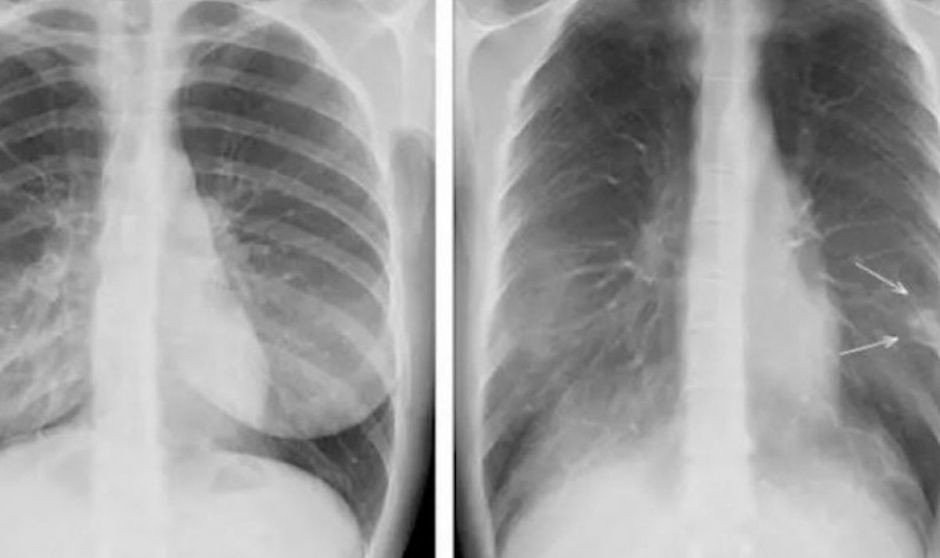

Las fracturas pasadas por alto son una causa común de discrepancia diagnóstica entre la interpretación radiográfica inicial y la lectura final realizada por los radiólogos. Ante esta situación, un grupo de investigadores de la Faculta de Medicina de la Universidad de Boston ha realizado un estudio en el que la inteligencia artificial (IA) puede ayudar a los médicos a detectar fracturas en las radiografías.

"Nuestro algoritmo de IA puede detectar rápida y automáticamente rayos X positivos para fracturas y marcar esos estudios en el sistema para que los radiólogos puedan priorizar su lectura", ha explicado Ali Guermaiz, jefe de Radiología de 'VA Boston Healthcare System' y profesor de Radiología y Medicina en la Facultad de Medicina de la Universidad de Boston (BUSM, por sus siglas en inglés).

En ese sentido, Guermaiz subraya en el estudio que “el sistema también destaca las regiones de interés con cuadros delimitadores alrededor de las áreas donde se sospecha que hay fracturas. Esto puede contribuir potencialmente a reducir el tiempo de espera en el momento de la visita al hospital o la clínica antes de que los pacientes puedan obtener un diagnóstico positivo de fractura".

"La asistencia de IA ayudó a reducir las fracturas no detectadas en un 29 por ciento y aumentó la sensibilidad de los lectores en un 16 por ciento, y en un 30 por ciento para los exámenes con más de una fractura, al tiempo que mejoró la especificidad en un 5 por ciento", señala Guermaiz en el estudio.